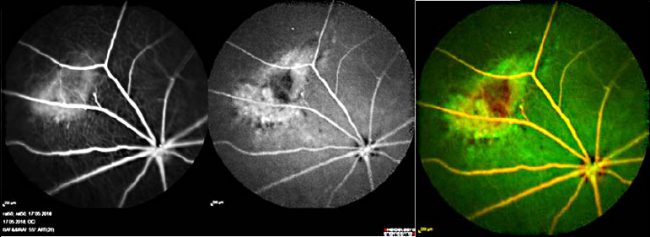

- Ocular mode of action

- Ocular mode of action